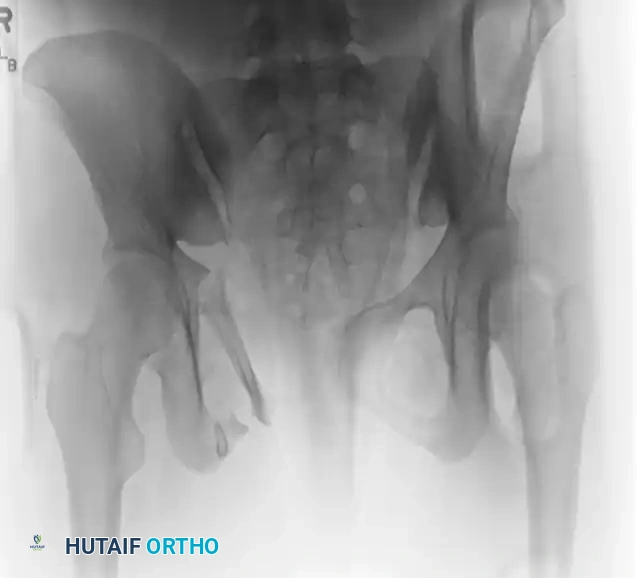

Understanding the underlying fracture pattern is paramount before applying an external fixator. The mechanism of injury dictates the vector of instability, which in turn dictates the required vector of reduction and frame construct.

The Tile classification assesses stability, dividing injuries into rotationally and vertically stable (Type A), rotationally unstable but vertically stable (Type B), and rotationally and vertically unstable (Type C).